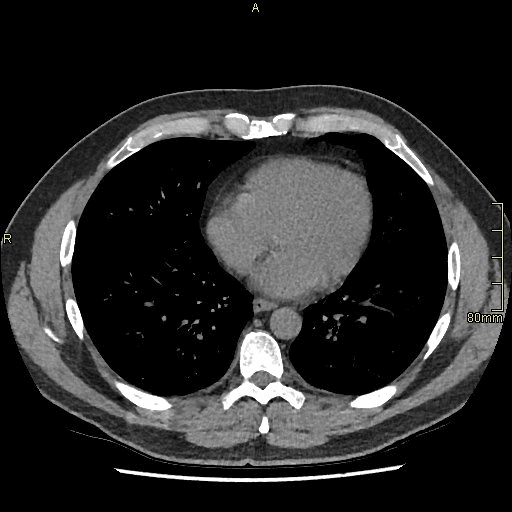

CT Abdomen/Pelvis - Non Contrast Axial